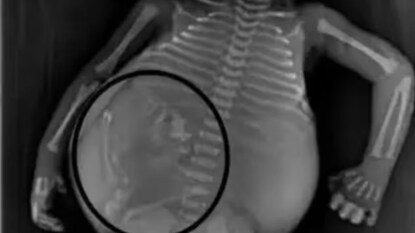

पण सीटी स्कॅन केल्यानंतर पोट फुगण्यामागील खरं कारण समोर आलं आणि सर्वांनाच धक्का बसला. डॉक्टरांना त्याच्या पोटात मऊ ऊती असल्याचं दिसून आलं. त्यात चरबी असते, तसंच हाडेही असतात. या आकृतीत त्यांना मानवी बाळासारखा पाठीचा कणा दिसला. मग त्यांना कळलं ही या बाळाच्या पोटात आणखी एक बाळ आहे.

सर्वात आश्चर्यकारक गोष्ट म्हणजे गर्भाशयात वाढणारं बाळ अर्धवट विकसित होतं. त्याच्या पाठीचा कणा आणि चेहऱ्याची हाडं तयार झाली होती. डॉक्टरांना आढळले की अम्नीओटिक सॅकमध्ये एक अर्ध-विकसित बाळ होतं. त्याच्या डोक्यावर केस होते आणि त्याचा पाठीचा कणाही चांगला तयार झाला होता. हातांना बोटं आणि पायांना अंगठेही होते.